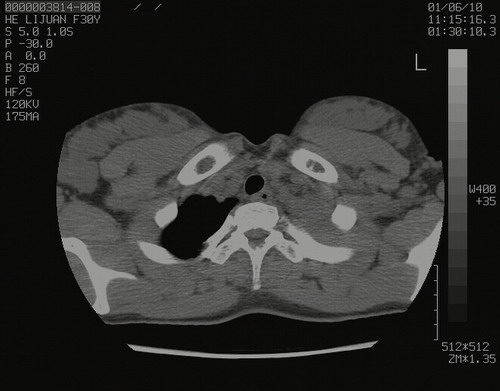

怀孕3个月时(2009-3至4月间),自述突感左侧前后胸疼痛1天,以前胸明显,随后偶感闷痛,余未见异

左肺尖脊柱旁沟肿块,境界清楚,边缘光滑,密度不均,内有多发点片状钙化,考虑良性肿瘤,骨软骨瘤或神经源性肿瘤可能,肺错构瘤不除外。

左后上纵隔见一类圆形肿块影,外侧边界清,密度不均匀,内可见点状钙化影,增强呈不均匀强化,考虑神经源性肿瘤可能。期待病理结果。